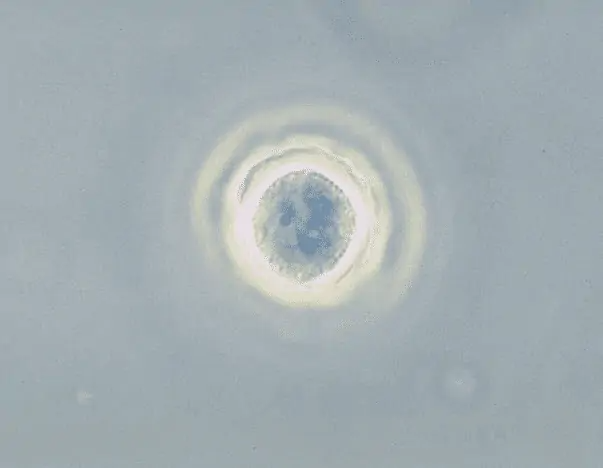

6. Acanthamoeba

Loại ký sinh trùng amip này gây ra bệnh viêm não amip có u hạt (GAE), một căn bệnh dẫn đến sưng não. Khoảng 95% bệnh nhân bị GAE bị amip giết. Tuy nhiên, không phải mọi người nhiễm Acanthamoeba đều bị GAE và một số bệnh nhân có thể không bao giờ xuất hiện bất kỳ triệu chứng nào.

Ký sinh trùng có thể được tìm thấy trong đất, bể bơi được khử trùng bằng clo, nước máy, trên bề mặt kính áp tròng, nước đóng chai và thiết bị điều hòa không khí và nó có thể xâm nhập vào cơ thể người qua mắt, vết loét, vết thương và hốc mũi.

Khi Acanthamoeba nhiễm vào mắt, tình trạng này được gọi là viêm giác mạc. Người mắc bệnh phải đối mặt với tình trạng đau mắt dữ dội, nhìn mờ, đỏ mắt, loét giác mạc và nhiều vấn đề liên quan đến mắt khác. Trong trường hợp này, chẩn đoán sớm là vô cùng quan trọng vì nếu không được điều trị, bệnh nhân có thể bị mù vĩnh viễn do nhiễm trùng.